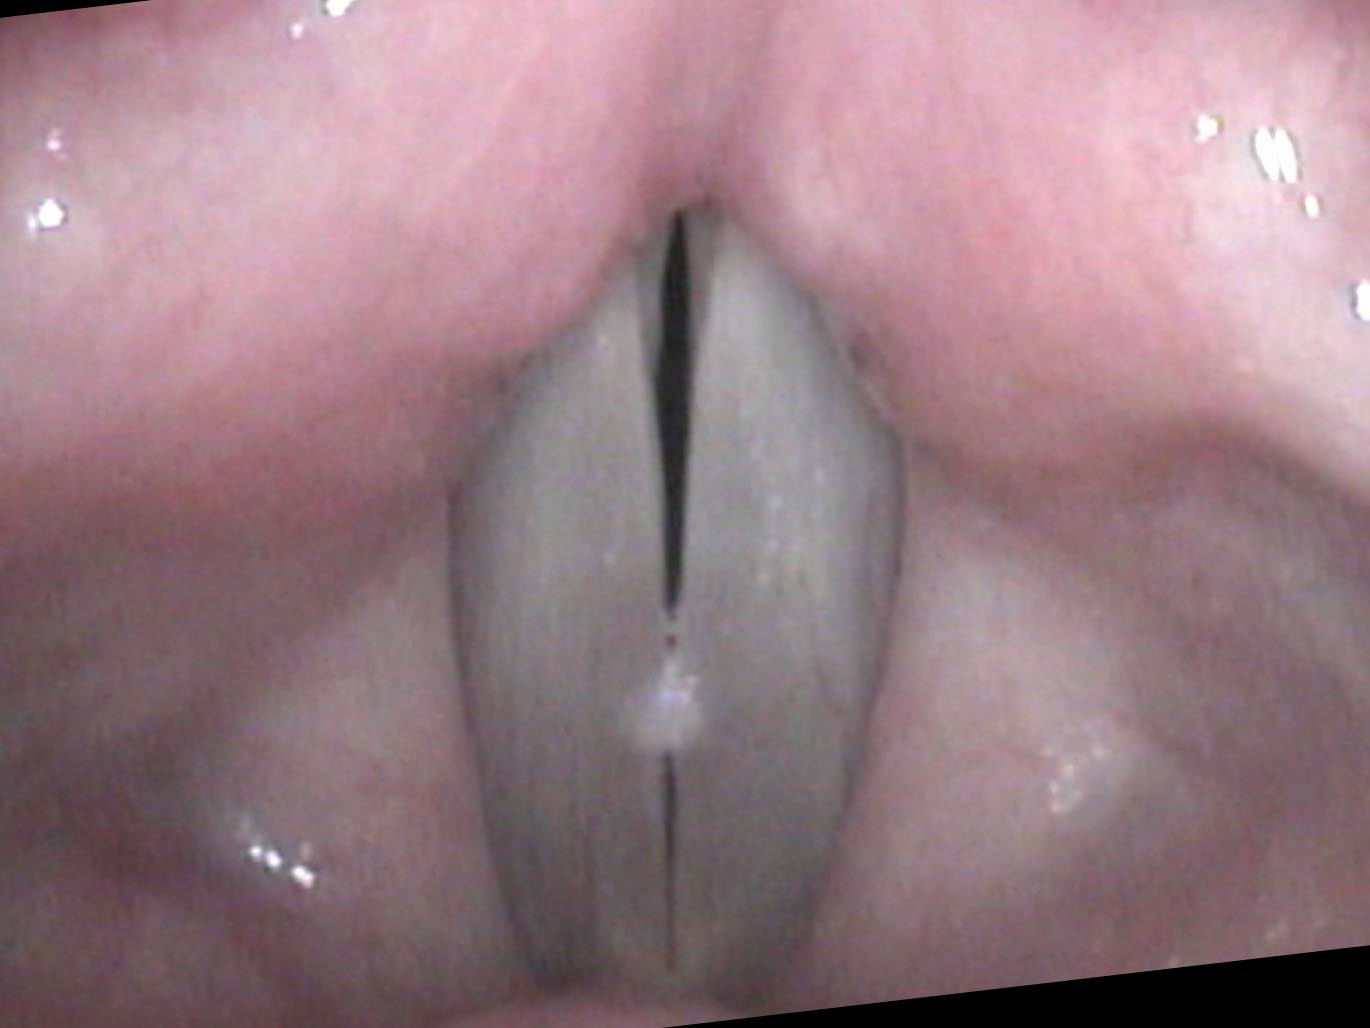

The vocal capabilities reveal a low speaking pitch and a consistent onset delay on swelling testing. On endoscopy there are bilateral nodules with ectatic blood vessels nearby — evidence of repeated micro-hemorrhage into the cord over time. His wife’s observation was correct: he sounds hoarse all the time, and the swellings will persist as long as he continues yelling.

A nodule represents a thickening of the mucosa — the outer layer of the vocal cord. It is analogous to a callus on the hand.